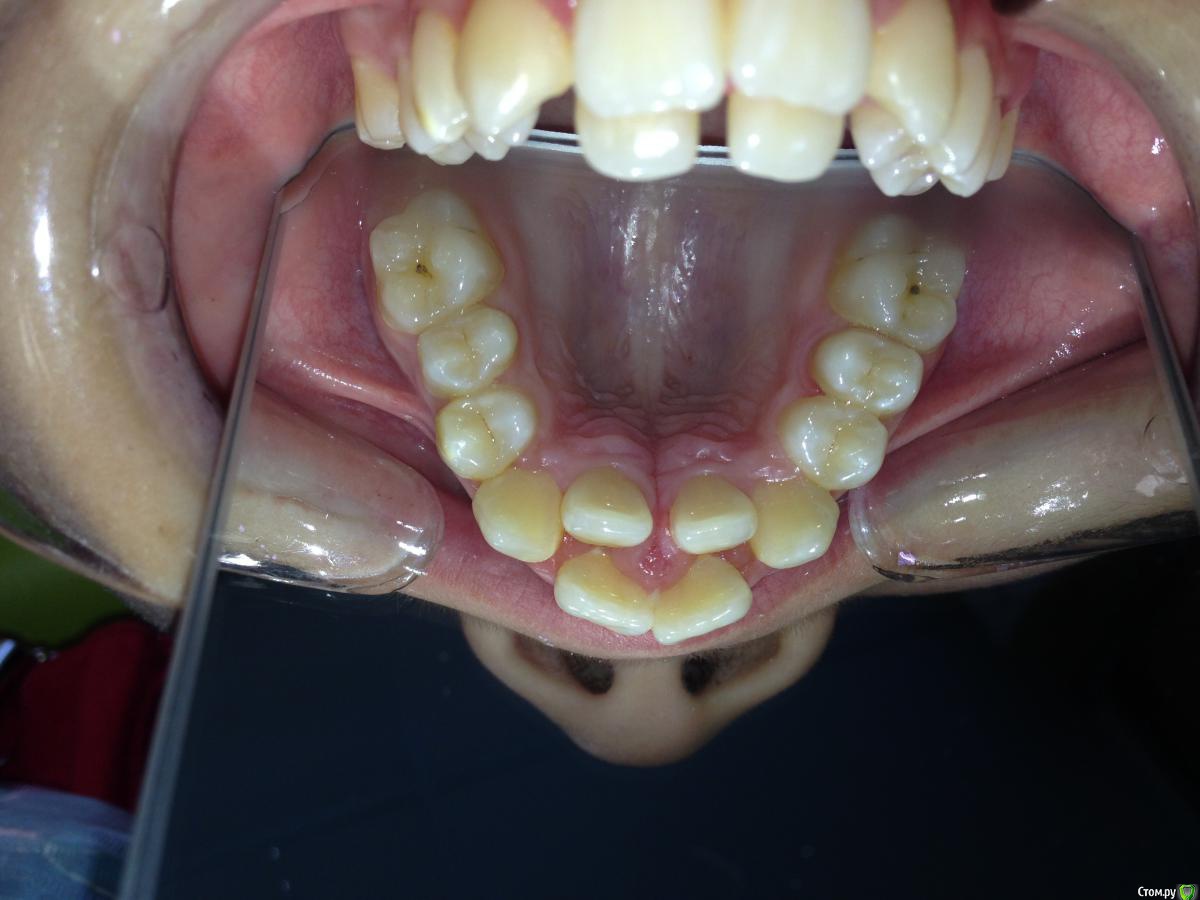

Алевтина Петровна Опубликовано 26 августа, 2015 Поделиться Опубликовано 26 августа, 2015 Всем добрый вечер. Я начинающий ортодонт. Надеюсь,что вы поможете с планом лечения. Пришел пациент. 13 лет. Ситуация по мне непростая, но очень интересная. Ссылка на комментарий

Алевтина Петровна Опубликовано 26 августа, 2015 Автор Поделиться Опубликовано 26 августа, 2015 Прикрепляю дополнительные фото, извините за качество. Это моя первая публикация, пытаюсь разобраться. Ссылка на комментарий

Molox Опубликовано 26 августа, 2015 Поделиться Опубликовано 26 августа, 2015 Ставьте Дерихсвайлера, вопрос с дефицитом места отпадет сам собой. И потом на брекетах по накатанной. 2 Ссылка на комментарий

Yana guapa Опубликовано 26 августа, 2015 Поделиться Опубликовано 26 августа, 2015 как только прорежутся нижние 7-ки, я бы сразу послала бы на удаление зачатков нижних 8-ок. аппарат RPE конечно можно поставить. но 13 лет - критический возраст. стоит вопрос о необходимости SARPE. иначе можем получить результат только на уровне зубов (просто их наклонт будет). а Если хотим реально челюсть расширить, то лучше вместе с хирургом. И по срокам быстрее , и результативнее и стабильнее. 1 Ссылка на комментарий

Maverick Опубликовано 29 августа, 2015 Поделиться Опубликовано 29 августа, 2015 Хайрекс вплоть до 15 лет дает хороший скелетный эффект. Никакого хирурга не надо. Зачем простое занятие превращать в травматичное, да и порой на которое родители не дают согласие. Мальчик такого возраста отличный пациент для скелетного расширения верхней челюсти. Как вариант посмотреть по позвонкам на трг на скелетный возраст , а судя по его трг, у него он еще есть. Так что вам ничего не мешает работать. Ссылка на комментарий